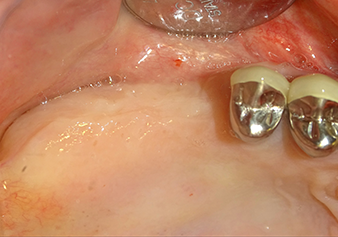

Implantation and prosthetic restoration

To move the augmentation material in the direction of the maxillary sinus atraumatically, the implant was inserted very slowly by hand (Fig. 9). In the process, the membrane was pushed in the cranial direction once again. After two months, the surgical site healed without irritation. Six months later, the x-ray check showed a significant increase in opacity as an indication of ossification (Fig. 10). The prosthetic restoration was carried out with a metal-ceramic crown.

Situation after insertion of the implant

Fig.9: Situation after insertion of the implant (length: 10 mm, prosthetic platform: 6.5 mm) immediately before suturing.

The x-ray check shows a largely homogeneous peri-implant hard tissue structure

Fig.10: A good six months later, after the definitive crown had been incorporated, the x-ray check shows a largely homogeneous peri-implant hard tissue structure.